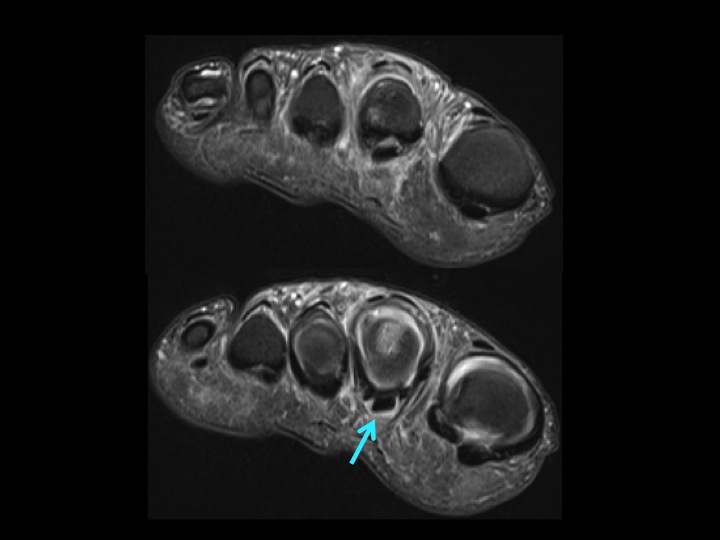

There is flattening of the dorsolateral 2nd MT head (white arrow) with subchondral marrow edema; minimal marrow edema at the base of the 2nd toe (yellow arrow) but not DJD. There is a subtle tear at the midline and lateral paracentral insertion of the plantar plate (red arrows). The tear is near the capsular recess, which is not wide, but there is fluid signal communicating between the MTPJ and the flexor tendon sheath (blue arrow 2nd slide) which is pathologic. 3rd slide shows lateral capsule tear. Ive seen this combo before: Freibergs and PP tear. Makes me think about meniscal root tear and what was formerly-known-as-SONK, and wonder whether it is the Freibergs that leads to the PP/capsule tear or vice versa. Thoughts?

Freibergs Infraction with 2nd MTPJ plantar plate and lateral capsule tear